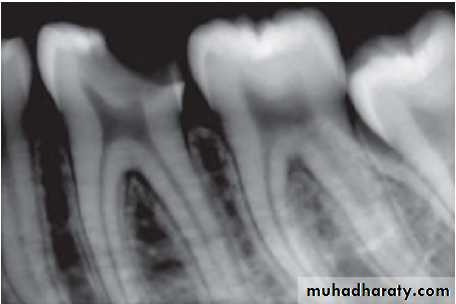

2. Calcifications

In calcific degeneration, part of the pulp tissue is replaced by calcific material. Mainly three types of calcifications are seen in pulp:Dystrophic calcification: occur by deposition of calcium salts in dead or degenerated tissue. The local alkalinity of destroyed tissues attracts the salts.

Diffuse calcification: They are generally observed in root canals. The deposits become long, thin and fibrillar on fusing.

Denticles/pulp stones. These are usually seen in pulp chamber.

Classification

According to location:•Free

• Embedded

• Attached

According to structure:

•True• False

True denticles: It is composed of dentin formed from detached odontoblasts or fragments of Hertwig’s enamel root sheath which stimulate and undifferentiated cells to assume dentinoblastic activity.

False denticles: Here degenerated tissue structures act as nidus for deposition of concentric layers of calcified tissues.